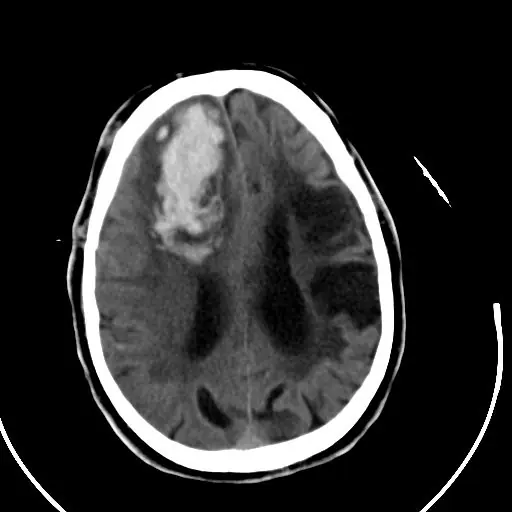

La ECV es causada por una interrupción en el abastecimiento de oxígeno de las arterias que van hacia y dentro del cerebro, ya sea debido a un bloqueo o una hemorragia.

Esto provoca la pérdida gradual de las funciones en la parte del cerebro que no tiene oxigeno y es una de las principales causas de muerte y discapacidad en el mundo.

Cuando un paciente sobrevive a esta lesión, su conducta y personalidad serán un reflejo del lugar y tipo de herida que sufrió.